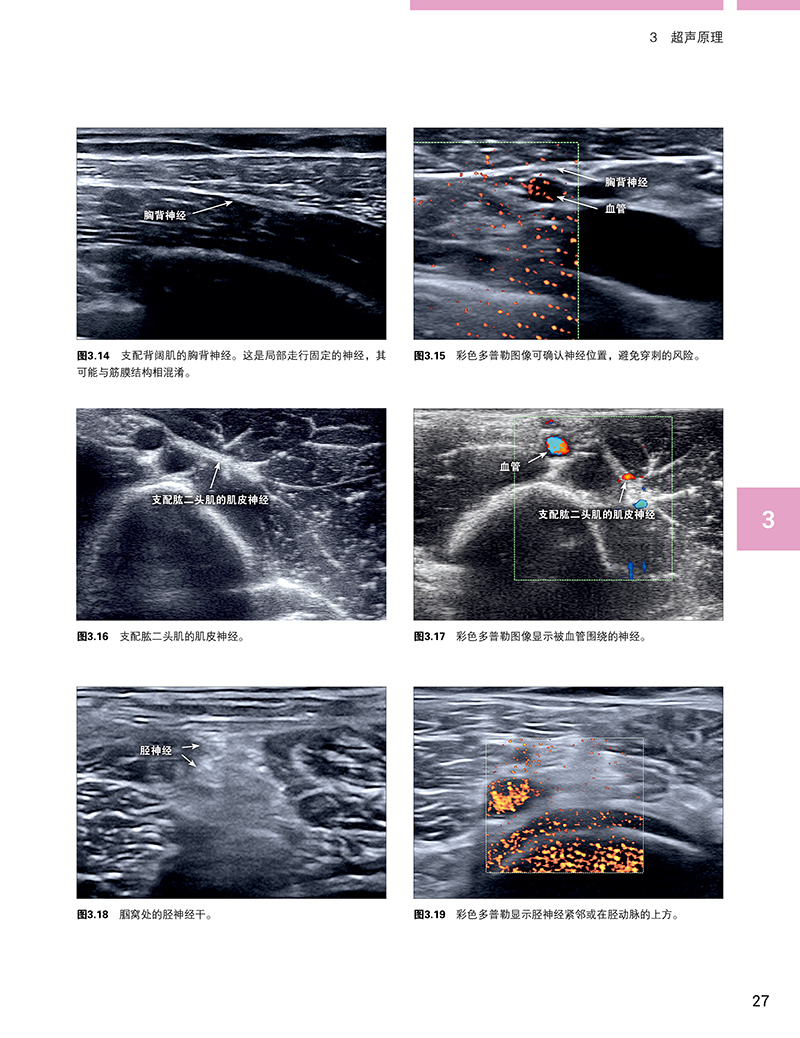

本书详尽介绍了超声技术及其在神经阻滞技术上的应用,以及相关的外周神经解剖。大量的超声图谱让读者熟悉如何在超声图像中确认这些神经及其分支。本书也对不同的神经阻滞技术(苯酚和冷冻神经阻滞)进行了详尽的临床病例报道。同时,还强调了利用利多卡因注射作为诊断性神经阻滞在肌痉挛治疗方面的价值,值得借鉴。